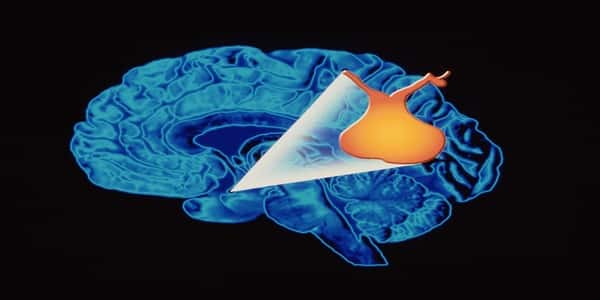

علاج أمراض الغدة النخامية تعتبر الغدة النخامية من أهم الغدد الموجودة في جسم الإنسان، وهي موجودة في منطقة أسفل الدماغ في جمجمة الإنسان، وتتكون هذه الغدة من ثلاثة فصوص، ويسمى الفص الأمامي بالنخامية الأمامية الذي يُعرف بالفص العادي، ومهمته إفراز هرمونات مثل الهرمون الموجه لقشرة الكظر وهرمون النمو وهرمون البرولاكتين والهرمون المنبه للغدة الدرقية والهرمون الملوتن، والفص الخلفي بالنخامية الخلفية الذي يقوم بتخزين الهرمونات التي يفرزها الفص الأمامي، بالإضافة إلى الفص الأوسط، والجدير بالذكر أن نظام هذه الغدة يتم بدقة عالية جداً، وتنظيم كبير، وسنقدم أعراض الغدة النخامية خلال المقال.